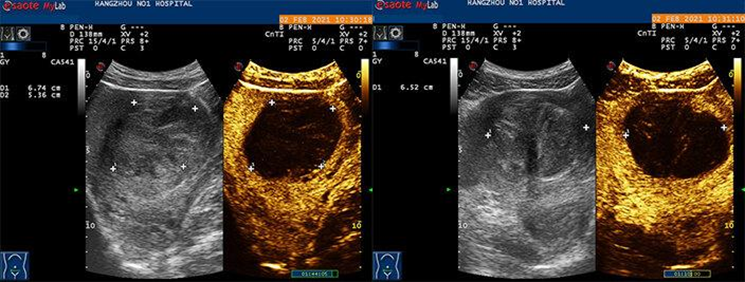

1. 附件区肿块:当附件区肿块内部有类实性成分时,可借助超声造影观察其大小、边界、内部回声情况、血流供应、有无活性组织,进一步判断肿块的良恶性及组织来源。

对于附件区多房囊性肿块,应选择血流最丰富的区域,对于附件区囊实性占位,则要选择实性部分为目标,建议显示部正常组织作为参照,如有造影剂灌注增强,提示有活性组织。

附件区肿块:无血流灌注的附件区占位,绝大部分为良性病变;如有造影剂灌注增强,则提示为活性组织。

卵巢良性肿瘤的强化程度低,强化时间晚,超声造影曲线为缓升缓降型;卵巢恶性肿瘤的开始增强时间、增强峰值时间和平均通过时间均明显短于卵巢良性肿瘤,增强峰值强度和增强曲线下面积均明显大于卵巢良性肿瘤;子宫内膜异位囊肿及畸胎瘤中的类实性成分往往没有增强;附件区脓肿造影时常表现为较典型的不均匀多房环状增强,环内呈无增强。